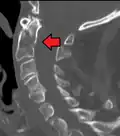

A fracture of the base of the dens as seen on CT -

Type 3 odontoid fracture -